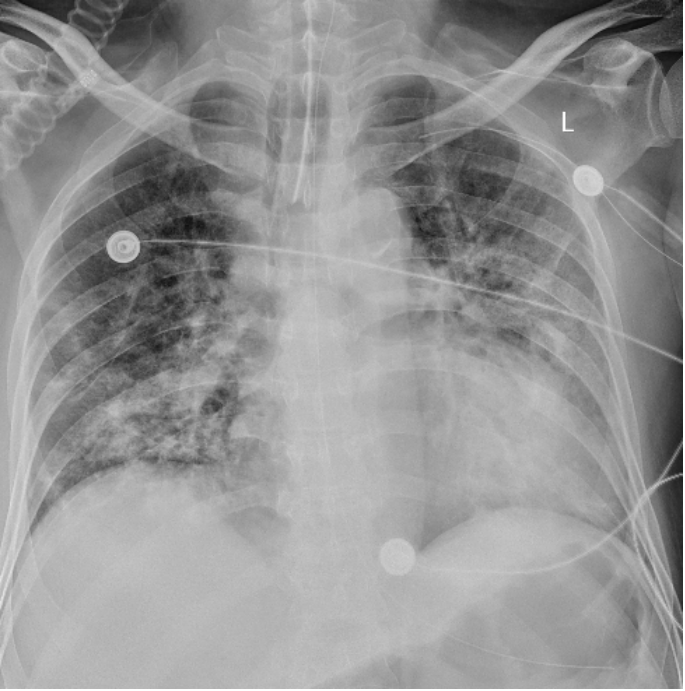

床边胸片可见双肺多发斑片影,考虑双肺感染(图4)

图片

图4 床旁胸片(2023-01-30)